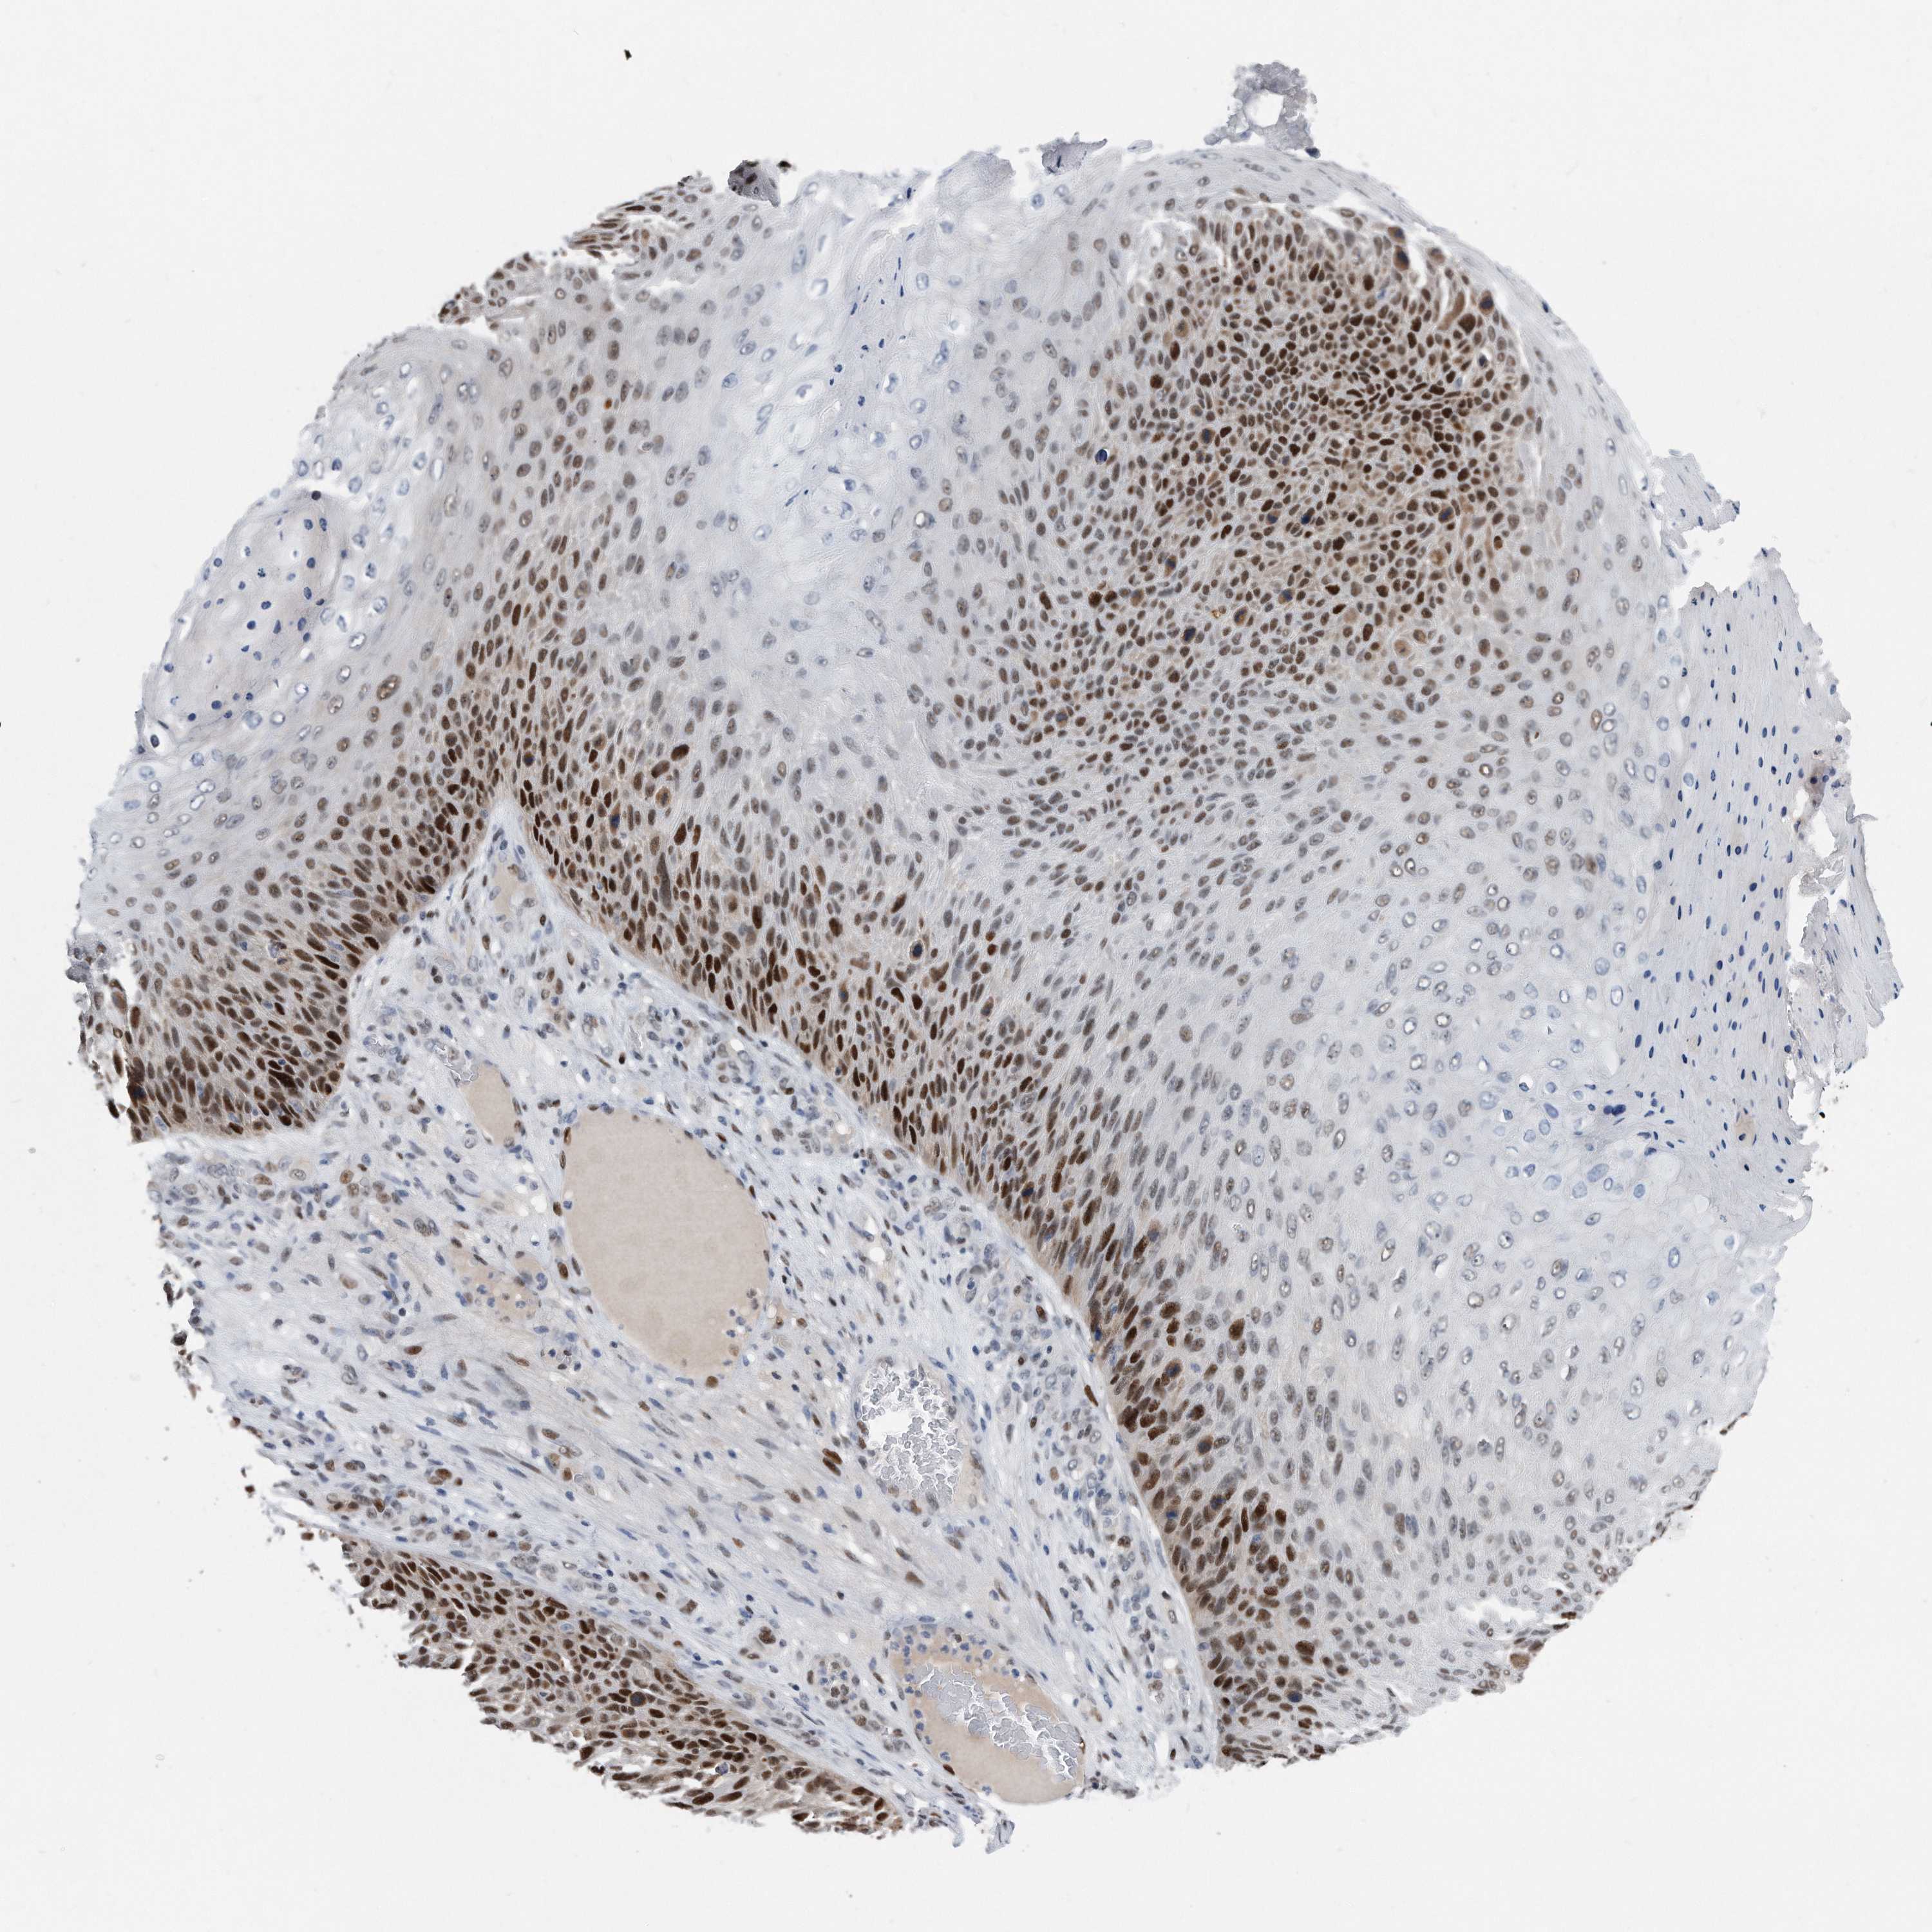

SKIN CANCER - Protein expressioni

A mouse-over function shows sample information and annotation data. Click on an image to view it in a full screen mode. Samples can be filtered based on level of antibody staining by selecting one or several of the following categories: high, medium, low and not detected. The assay and annotation is described here.

Antibody stainingi

Antibody staining in the annotated cell types in the current human tissue is reported as not detected, low, medium, or high, based on conventional immunohistochemistry profiling in selected tissues. This score is based on the combination of the staining intensity and fraction of stained cells.

Each image is clickable and will lead to virtual microscopy that enables deeper exploration of all samples and also displays staining intensity scores, fraction scores and subcellular localization as well as patient and tissue information for each sample.

HPA030521

HPA030522

HPA030523

CAB000148

CAB080240

CAB080241

CAB080242

Staining

High

Medium

Low

Not detected

Intensity

Strong

Moderate

Weak

Negative

Quantity

>75%

75%-25%

<25%

None

Location

Nuclear

Cytoplasmic/membranous

Cytoplasmic/membranous,nuclear

Basal cell carcinoma

Squamous cell carcinoma, NOS

Squamous cell carcinoma, metastatic, NOS